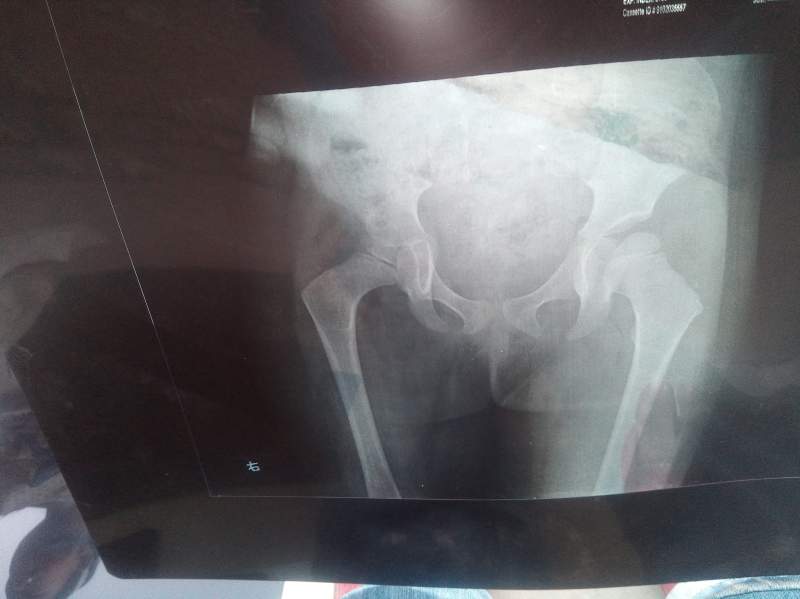

ÃÃÃÃÒòÖÎÁÆÑÓÎó£¬ÏÖ²¡Çé¼ÓÖØ£¬ÃæÁÙ̱»¾£»Õ÷Çó¸÷λ³æÓÑÌá³ö±¦¹óµÄÒâ¼û£¬½«¸Ð¼¤²»¾¡